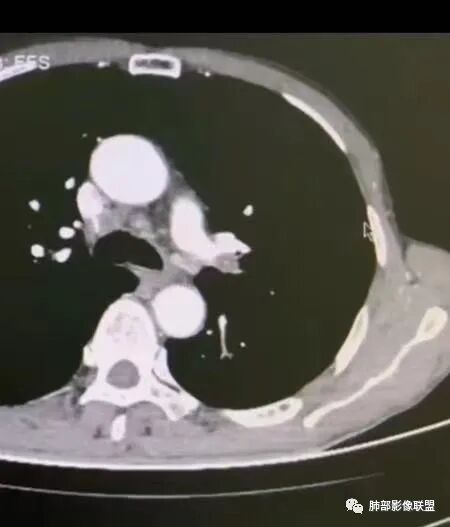

左肺及右肺中叶可见多发斑片状,条索及结节状高密度影,界不清,树芽征(+),中叶伴有支气管扩张,左肺下叶背段结节,周围伴毛刺,近端气管截断,实质密度不均匀,强化方式(看不清),8L,7及4区及左肺门见多发肿大淋巴结,老年男性,感染指标升高,呼吸道慢性病史,二元论,结核+左肺下叶背段恶性结节(鳞癌?)左肺下叶后基底段有新发感染?

左肺下叶沿支气管束走形实性病灶,增强后不均匀强化,低密度坏死或者粘液,周围肺野斑点状炎性病灶,左肺上叶尖后段及右下肺散在斑片状影。纵隔及左肺门多发肿大淋巴结。支气管镜左肺上叶舌段狭窄。首先考虑感染性病变,结核可能,鉴别肿瘤性病变,鳞癌;其次结节病。

8L引流区淋巴结明显肿大,左肺下叶背段结节恶性不除外

双肺多发索条,左肺下叶胸膜下软组织肿块,边缘光滑,平行于胸膜,左下肺门增大,见软组织结节,增强后均匀强化,考虑炎性肉芽肿性病变

左肺下叶团块状影,可见支气管截断征,增强轻度强化,左肺下叶可见纤维索条影,纵隔及左侧肺门可见淋巴结,左肺舌段支气管变窄,常规考虑黏液腺癌,局部合并炎症,鉴别结核,应该在这两个之间。

男,67,咳嗽、咳痰2年,加重10天。胸部CT:左肺下叶实性结节,边缘短毛刺、平直膨隆都有,近端支气管截断,胸膜牵拉,强化不均匀,纵隔、左肺门多发肿大淋巴结。左下叶远端尚可见树芽,胸膜下索条。考虑Ca,鳞?腺?鉴别TB、炎性结节。

这是血管